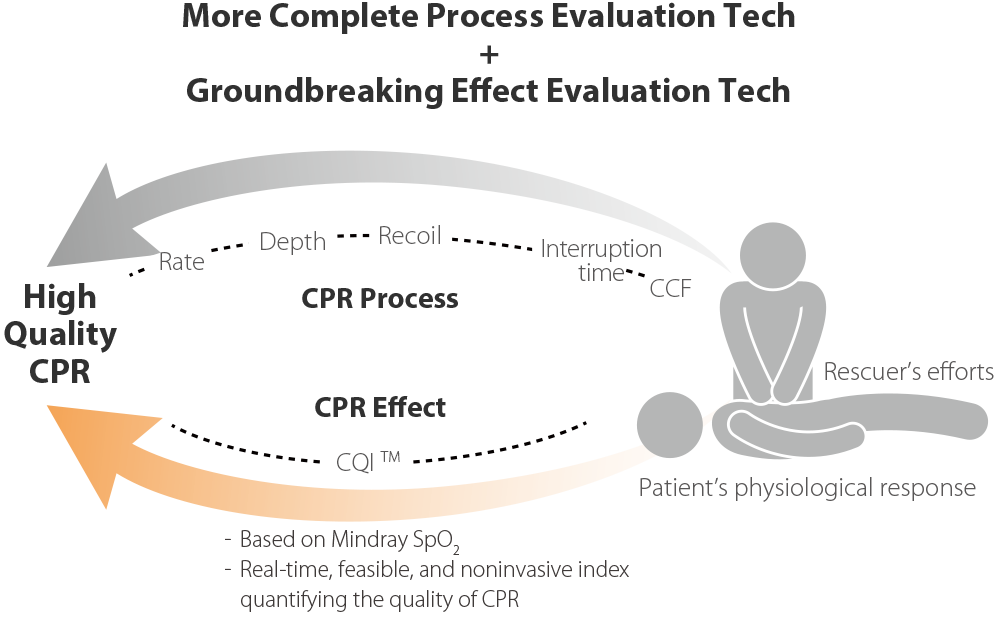

Rettungsdreieck, Umfassender

Schnellere Wiederbelebung